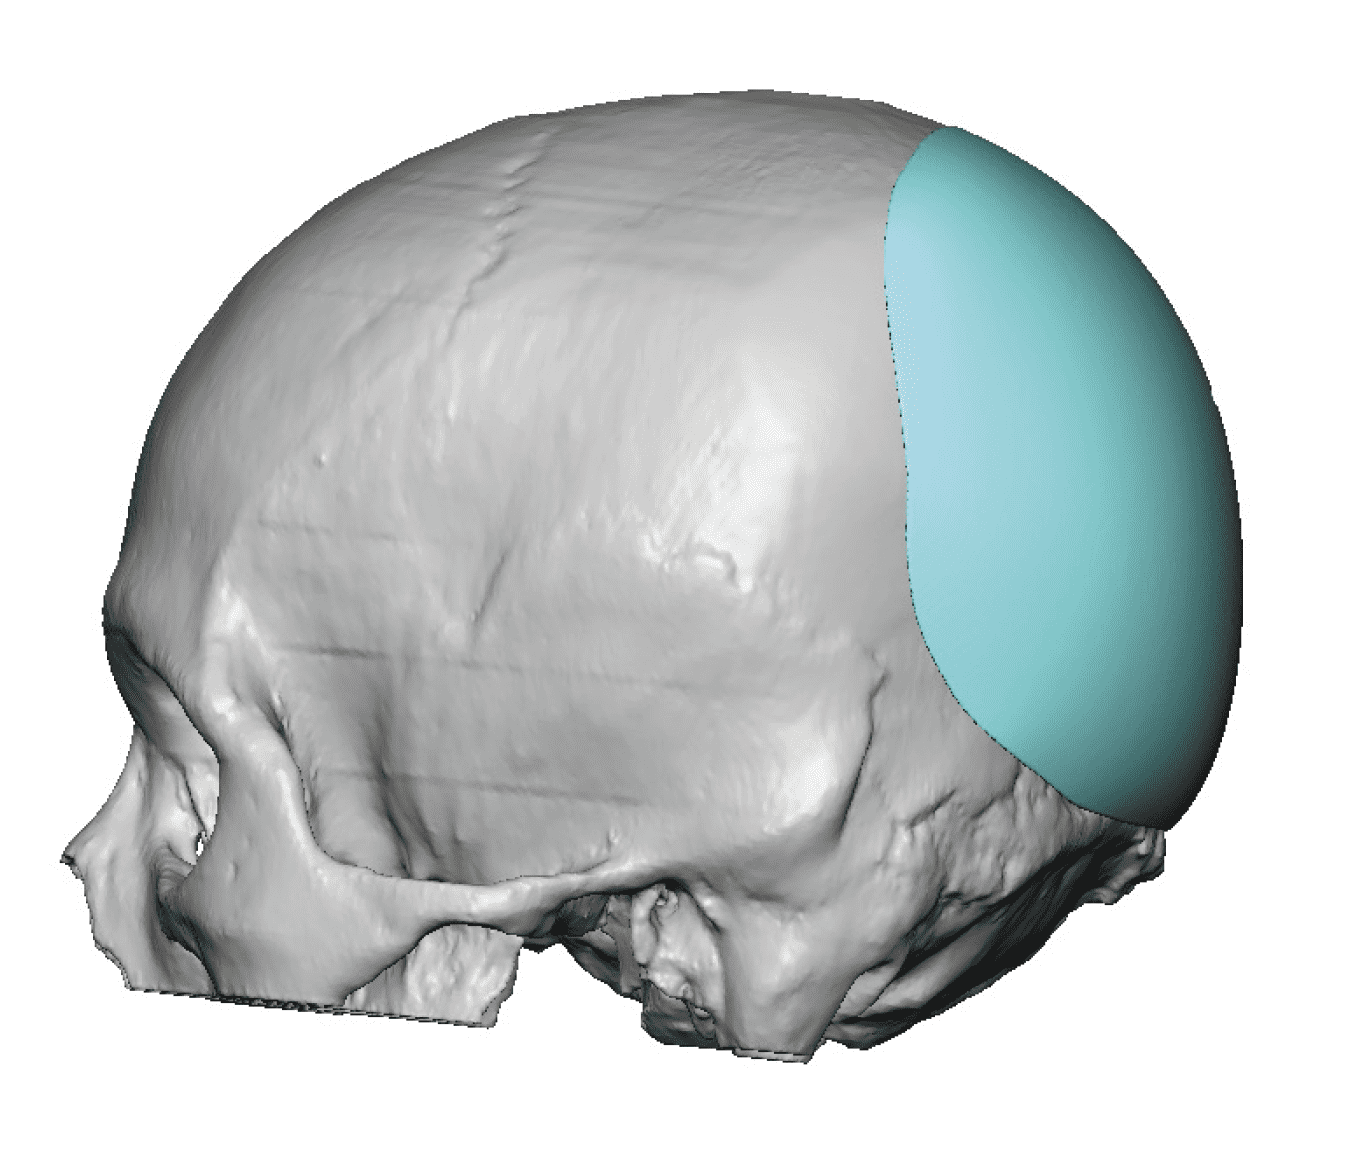

Desire for change of head shape from front view form an inverted V shape to a rounder and wider head shape.

Placement of custom extended forehead-temporal implants through incisions in the crease behind the ear. (he had a prior back of head skull implant which is green in the implant designs and which the head widening implants partially covered it)

Desire for change of head shape from front view form an inverted V shape to a rounder and wider head shape.

Placement of custom extended forehead-temporal implants through incisions in the crease behind the ear. (he had a prior back of head skull implant which is green in the implant designs and which the head widening implants partially covered it)